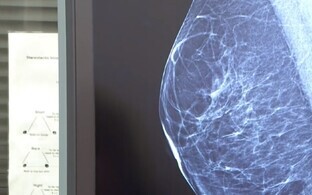

Один из изучаемых препаратов - лекарство от рака молочной железы Enhertu, которое уже некоторое время используется при лечении этого заболевания. Исследование показало, что эффект Enhertu статистически значим и приводит к реальным результатам: раковая опухоль пациентов не увеличивалась, и они жили дольше.